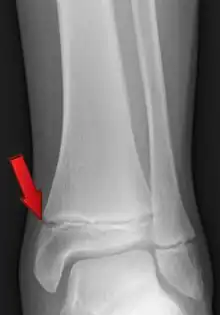

Fracturas

Se entiende por fractura una solución de continuidad en algún punto del hueso. Generalmente está causada por un traumatismo que provoca una tensión que supera la resistencia del hueso, causando su rotura. Tienen tendencia a consolidar gracias a los mecanismos naturales de autorregeneración que se inician con la formación de un callo de fractura. En muchas ocasiones el tratamiento consiste en realizar una inmovilización del área mediante vendaje de yeso para facilitar la curación natural y evitar el desplazamiento de los fragmentos.